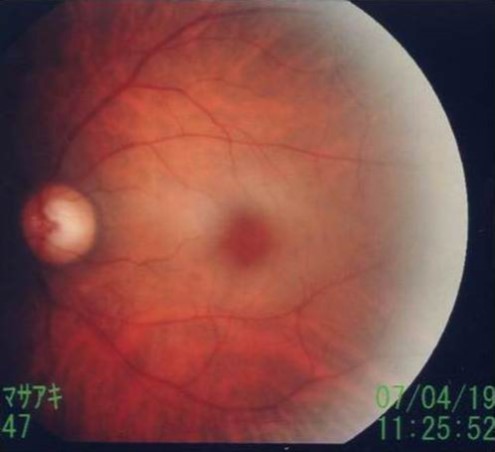

The following day (April 19, 2007), the corrected visual acuity of the left eye was 1.2; funduscopy showed a cherry red spot, characteristic of CRAO (Figure 4). Vision in the left eye subsequently improved gradually. At hospital discharge, although not perfect, vision had improved to the point where no impairment to daily activities was present.

Figure 4.Cherry red spot. Funduscopy showed a cherry red spot.

During the acute phase, within a few hours after onset, the retina appears normal, with characteristic findings developing within 24 h. The posterior pole of the retina is edematous and opaque, the retina thins at the fovea, and red coloration of the choroid is visible as a “cherry red spot” on funduscopy (Figure 4)8.